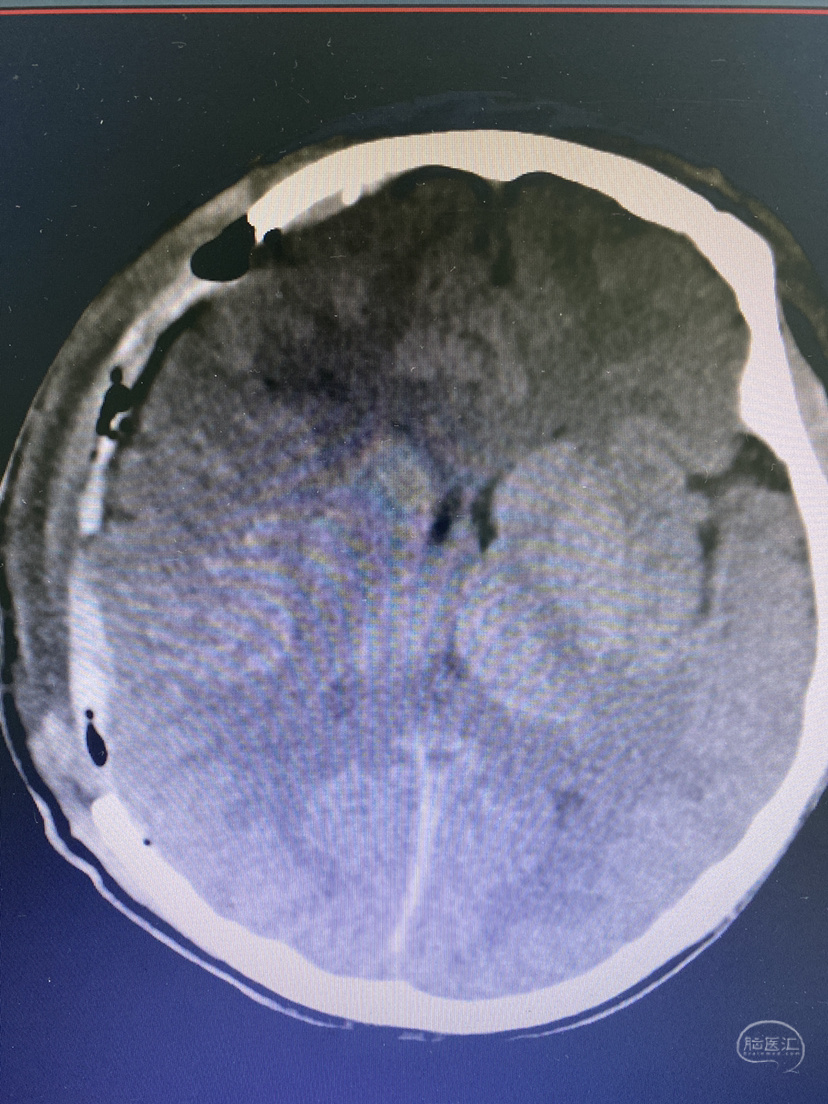

PEEK材料修补术后情况

术后一周出现皮下及硬膜外积液,但患者无神经症状。术中脑膜有破损,但严密缝合,常规负压引流,2天拔出引流管。但现在出现积液,考虑脑脊液吸收障碍?出血?予以穿刺抽液,呈陈旧性淡血性液体,不凝固,送细菌培养未见细菌生长,考虑脑脊液混合血液!不排除免疫原性积液,予以加压包扎,口服地塞米松,阿托伐他汀处理!